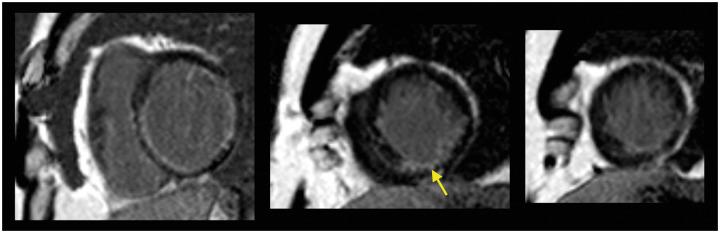

CASE SUMMARY

A 59-year-old male with a background history of coronary artery bypass graft surgery and previous PCI, presented with progressive chest pain on mild exertion, in the setting of a chronic coronary syndrome. Transradial coronary angiography revealed significant native three-vessel disease with CTO of right coronary, left anterior descending (LAD) and left circumflex arteries. Left internal mammary artery-LAD was widely patent. The previous LIMA-LAD stent at the anastomosis had a CTO with severe in-stent restenosis (ISR) at the distal end of the stent in the native LAD. The distal LAD was filled from bridging collaterals. Following discussion at the heart team meeting, he underwent successful complex PCI of LAD CTO via the LIMA graft at the site of ISR of previous LIMA-LAD anastomosis stent, which was finally treated with drug-coated balloon (DCB) angioplasty.

一名59岁男性,有冠状动脉旁路移植手术和既往PCI病史,在慢性冠状动脉综合征背景下,轻微活动时出现进行性胸痛。经桡动脉冠状动脉造影显示严重的三支血管病变,右冠状动脉、左前降支(LAD)和左旋支动脉均为CTO。左乳内动脉-LAD广泛通畅。先前LIMA-LAD吻合处的支架在LAD近端支架远端出现CTO并伴有严重的支架内再狭窄(ISR)。LAD远端由桥接侧支供血。在心脏团队会议讨论后,他在先前LIMA-LAD吻合支架ISR部位经LIMA移植成功进行了LAD CTO的复杂PCI,最终采用药物涂层球囊(DCB)血管成形术进行治疗。